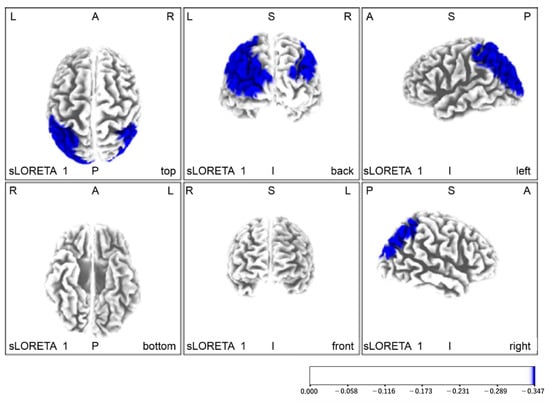

| Pre-intervention (red) < Post-intervention (blue) | |||||||

| blue | −40 | −55 | 60 | Left parietal lobe | supramarginal gyrus | 40 | 6.76 |